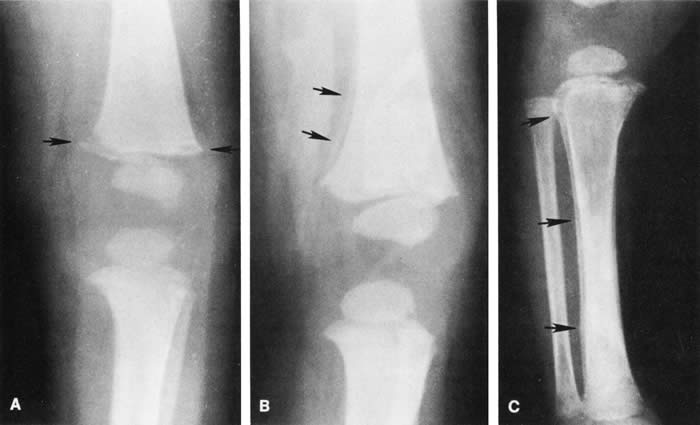

SHAKEN BABY SYNDROME The triad of the SBS includes brain injury usually with hemorrhage, ocular injury, and skeletal injury. These children often have no external signs of trauma. The infant and young child are particularly vulnerable because of their relatively large head, weak cervical musculature, large size of the cranial vault in relation to the size of the brain,3 and immature, unmyelinated brain. Violent shaking causes repetitive anteroposterior and side-to-side disorganized head movement with abrupt acceleration-deceleration forces.7,17,18,19 The magnitude of acceleration-deceleration forces needed to cause brain and eye injuries in humans is extreme but not exactly quantified.20 Although in Caffey's original description, he inferred that normal play activities could cause SBS-like injuries, we now recognize that this is not the case.21 Abusive head trauma is the most common type of child abuse resulting in death,22 although it represents only 3% to 5% of all cases referred to child abuse teams.23 Assault represents more than half of all traumatic brain injury in the first year of life and 90% of brain injuries between 1and 4 years of life. The average age of SBS victim is between 5 and 10 months,22–31 with most children younger than 2 years of age.22,25,26,30 Victims up to 5 years old are rare. The mortality rate of SBS, based on studies with more than 10 patients, is approximately 8% to 61%,23 although this may be a reflection, in part, of separation or imprisonment of perpetrators after the first incident. Recidivism rates are high. The most common perpetrators of SBS are biological fathers and biologically unrelated boyfriends of the mother.22,26,30,32,33 Babysitters, females 4.4 times more often than males,22 are the perpetrators in 4% to 20% of cases.22,26,33 Biological mothers commit this crime in 5% to 12% of cases.22,26,33 Only a minority (10% to 15%)23,33 of perpetrators confess, although it may be as high as 43%34 in fatal cases. SHAKEN BABY SYNDROME: SYSTEMIC MANIFESTATIONS Brain injury in SBS is common: Subdural hemorrhage is found in 10% to 93%, subarachnoid hemorrhage in 10% to 72%, posterior interhemispheric blood in 20% to 100%, stroke in 12% to 50%, intraparenchymal hemorrhage in 5% to 30% and parenchymal tears in 0 to 100%. 23,24,26,29,35 Increased intracranial pressure or cerebral edema is found in 44% to 85%.23,35 The wide variation in incidence figures reflects the nature of the study populations: findings at presentation, in survivors, or at autopsy. At autopsy, subdural hemorrhage, subarachnoid hemorrhage, and cerebral edema are the most consistent findings.21,34,36,37 Although one study using a mechanical model and autopsy investigation suggested that blunt head impact is required to generate the forces necessary to cause the brain injury of SBS,38 a wealth of clinical and pathologic investigations indicate that shaking alone can cause significant injury and even death. Perhaps calculation of forces does not allow for a full understanding as cellular and biochemical responses to shearing stress along with other factors such as anemia and hypoxia may play an important role that cannot be modeled. Violent shaking causes shearing forces that tear the bridging veins running from the cortex to the dural venous sinuses, resulting in subdural and subarachnoid hemorrhage. Shearing also causes diffuse axonal injury with secondary brain edema.39,40,41,42 The diagnosis of brain injury is usually confirmed with computed tomography (CT) scan. However, the CT scan may initially be normal or show edema without hemorrhage. Magnetic resonance imaging (MRI) may be useful to find hemorrhage not visualized on CT43 and to date the findings seen on CT. The long-term prognosis for children with brain injury secondary to SBS is poor. In one study, only 28% of survivors had normal neurologic exams on discharge from the hospital; this figure decreased to 8% to 14% in long-term studies.22 Late findings seen on imaging studies include cerebral atrophy, hydrocephalus ex vacuo, chronic subdural effusion, and encephalomalacia. Patients may have quadriplegia, diplegia, hemiplegia, mental retardation, developmental delay; learning disability, seizures (7% to 65%), and psychiatric/behavioral issues(28% to 50%).23,24,26,30,44 Skull fractures occur in 9% to 31% of shaken babies,23,30 with the parietal and occipital bones most affected. The characteristics of skull fractures that are highly suggestive of abuse include branching, stellate, crossing suture lines, multiple, greater than 5 mm wide, or progressively expanding fractures in a child less than 3 years of age.29 Rib fractures are the most common bone injury in SBS, and are usually posterolateral due to the perpetrator's hands grasping the child. Long bone fractures affect the tibia, forearm bones, femur, or humerus in decreasing order of prevalence. The characteristic metaphyseal fracture, which rarely occurs in young children except in the setting of abuse, results in a “corner” or “bucket handle” chip fracture at the end of the bone (Fig 9). Other injuries seen in SBS include hemorrhagic stripping of the periostium, spiral fractures, and nonsupracondylar humerus fractures—all due to shaking while the infant is held by an extremity, causing the long bones to be twisted and broken.29,30 SHAKEN BABY SYNDROME: OCULAR MANIFESTATATIONS Retinal Hemorrhages Retinal hemorrhage is the most common ocular manifestations of SBS. The incidence of retinal hemorrhages in SBS varies in published reports. This variation is in part due to methods of examination (ophthalmologists vs pediatricians, dilated vs undilated pupils) and the population studied. Overall, the incidence varies from 30% to 100%.18,21,30,38,51,52,53 The incidence in studies including children with abusive head trauma not due to shaking is lower than in studies only involving SBS. In postmortem studies, the incidence of retinal hemorrhages approaches 100%.34,51,54,55 Findings range from a normal fundus to a small number of scattered intraretinal hemorrhages in the posterior pole to massive, confluent hemorrhages from the posterior pole to the ora serrata.(Fig. 10) The hemorrhages may be subretinal, deep intraretinal (dot/blot), nerve fiber layer (flame shaped) or preretinal.19,45 Intraretinal hemorrhages are more common than preretinal or subretinal hemorrhages.32,46 Preretinal hemorrhages must be distinguished from traumatic retinoschisis (see later), which has particular diagnostic significance. White-centered retinal hemorrhages, although classically associated with endocarditis, can occur in any condition that causes retinal hemorrhages, including SBS. Vitreous hemorrhage may be small to massive, and may occur secondary to escape of blood from intraretinal collections or from torn vessels.19 Although vitreous hemorrhage may occur at the time of injury, it may also be a delayed finding occurring 1 to 3 days or more after the initial trauma.47,48 Retinal hemorrhages may be associated with papilledema in SBS. However, papilledema is seen in less than 10% of shaken babies.35, 49 These small, flame-shaped hemorrhages on and radiating around the optic nerve are not necessarily caused by shaking and may be seen in papilledema from any cause. However, retinal hemorrhages associated with SBS may be seen on the optic disc in the absence of papilledema.50 Retinal hemorrhage is usually bilateral but may also be asymmetric or unilateral. Retinal hemorrhage can not be dated with any precision and, therefore, should not be used to help determine when the abusive event occurred.46,47,56,57,58,59 At best, generalizations may be made with wide intervals. For example, intraretinal hemorrhages do not last months, and blood in schisis cavities does not go away in days. Retinal scars or optic atrophy do not form in days. The pathophysiologic mechanisms of retinal hemorrhage in SBS are varied. Vitreous and perhaps orbital shaking is likely to be involved in most of the vitreoretinal injuries. In children, the vitreous is well attached to the retina at the macula, blood vessels, and the periphery. Shaking of an infant causes the vitreous to shake, which, in turn, applies shearing forces to the retina at points of firm attachment. These shearing forces at the macula may split the retina at any layer, causing the formation of a cystic cavity, which may be filled partially or completely with blood (Fig. 11). This traumatic retinoschisis has been well documented in abuse cases by ultrasound, electroretinogram, and pathology.34,58,60,61,62,63,64 Histopathology reveals a widening of the retinal layers or a stripping of the internal limiting membrane. The vitreous may stay adherent or detach. Clinically, to recognize this important finding in SBS, the examiner may observe a hemorrhagic or hypopigmented curvilinear edge to the schisis cavity, with or without a fold in the retina (Figure 11).50,65,66 Recognition of this edge helps distinguish retinoschisis from subhyaloid hemorrhage. However, subhyaloid hemorrhage, which may have originated from blood breaking out of a schisis cavity, may obscure the underlying schisis. It is important to follow any potentially shaken child with preretinal blood in the macula until that blood has cleared as the signs of schisis may be unmasked as the blood resorbs thus confirming the diagnosis of SBS. The retinal fold or hypopigmented line may be a complete circle or just an arc. In the long term, these patients may have surprisingly few sequelae and good vision as the cavity flattens spontaneously. There may also be findings of permanent curvilinear, hypopigmented scars or retinal folds. These provide clues to prior abuse.67